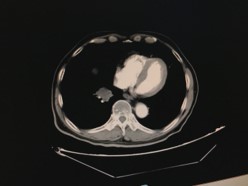

瑞戈非尼 160mg Qd po

2019年07月SD

2019年10月SD

2020年01月 略增大